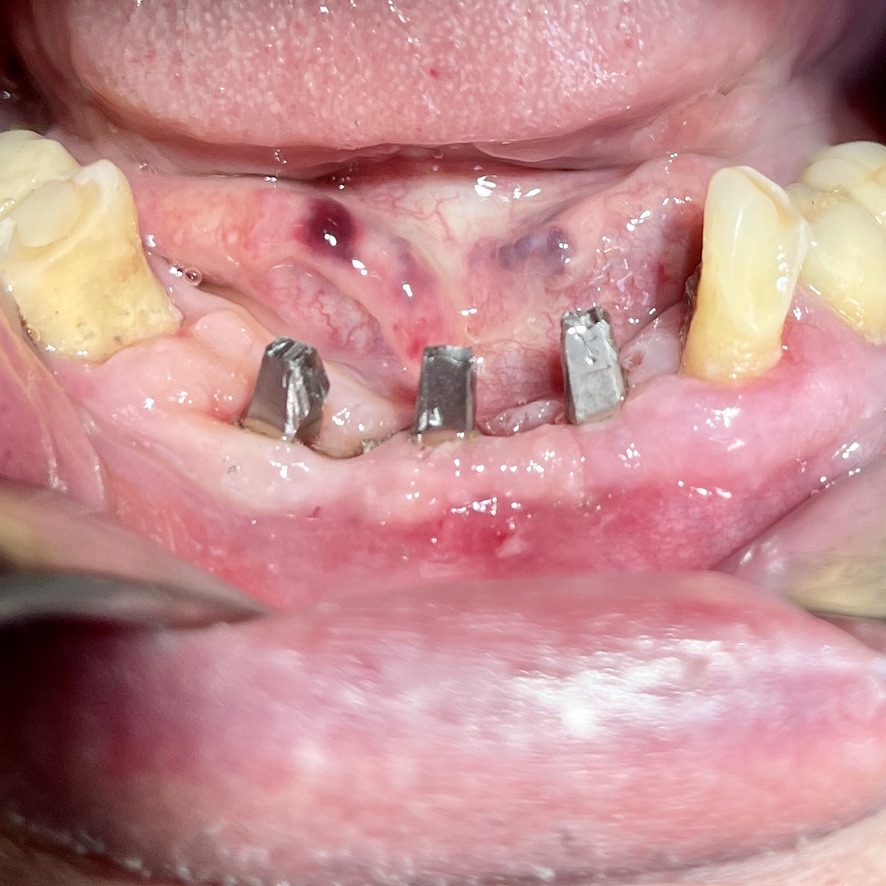

CASO CLINICO : Riabilitazione del 28/04/2021

In particolare considero notevoli i seguenti aspetti:

• 10 grave parodontopatia del settore inferiore

• 11 problematiche igieniche

• 12 insuccesso implantare di impianto di Tramonte inferiore, impianto precedente al 2004, nel quadro della generale parodontopatia

• 13 l’inserimento dei tre impianti non ha comportato innesti di osso o di tessuti connettivali.

• 14 Non ha reso necessari scollamenti

• 15 Non è stata necessario isolare le emergenze dei nervi alveolari inferiori

• 16 Trattandosi di osso ad elevata densità si è ricorsi alla fresa elicoidale, strumento raramente utilizzato da noi perchè non necessario e perchè ci sono zone in cui il suo utilizzo comporta rischi chirurgici per noi non accettabili. Inoltre questa fresa asporta quantità discrete di osso che preferiamo resti dove la natura lo ha messo. Interessante il fatto che il diametro della fresa è di solo 2 mm

• 17 Trattandosi di osso denso, gli impianti utilizzati avevano un diametro di soli 4 mm dopo maschiatura col corrispondente maschiatore.

• 18 Al controllo del 3/5/2021 il paziente non è gonfio e riferisce che mangia finalmente bene.

• 19 Inizio intervento implantare alle 8.45. fine intervento implantare alle 9.36.

• 20 Cementazione del provvisorio, confezionato al momento, ultimata alle 10.30. durata totale permanenza del paziente in ambulatorio1,45 ore.

Le immagini forniscono nelle didascalie ulteriori informazioni.